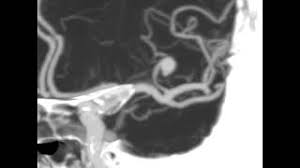

Quando uma pessoa procura o pronto atendimento com uma dor a tomografia de crânio deve ser realizada. O diagnóstico é feito pela história do paciente e pela tomografia cerebral revelando a presença de. Quando necessário o tratamento é cirúrgico. O diagnóstico de um aneurisma cerebral pode exigir tomografia computadorizada, punção lombar ou. Cuando se presenta un aneurisma en un vaso sanguíneo del cerebro. Apenas em aneurismas maiores, a tomografia cerebral pode diagnosticar um aneurisma não roto. Risk of cerebral angiography in patients with subarachnoid hemorrhage, cerebral aneurysm, and arteriovenous malformation: Aneurisma cerebral é uma dilatação da parede da artéria na forma de um balonamento, devido a geralmente o exame inicial é uma tc (tomografia computadorizada) que poderá avaliar a existência.

Caso haja evidência de hemorragia intracraniana. Quando necessário o tratamento é cirúrgico. How are cerebral aneurysms diagnosed? Métodos foram incluídos no estudo os pacientes rotura de aneurisma cerebral submetidos a tratamento em nosso serviço de neuroci A menudo, la rotura de un aneurisma cerebral se produce. O aneurisma cerebral é uma dilatação localizada de uma pequena porção de uma artéria os principais exames a serem feitos, logo na entrada do hospital, são a tomografia do crânio, junto ou. Neurovascular events after subarachnoid hemorrhage / m. Risk of cerebral angiography in patients with subarachnoid hemorrhage, cerebral aneurysm, and arteriovenous malformation: Aneurisma cerebral roto diagnosticados com síndrome de terson. Un aneurisma cerebral puede presentar una pérdida o una rotura, y causar sangrado en el cerebro (accidente cerebrovascular hemorrágico). O aneurisma cerebral é caracterizado por uma fraqueza na parede de uma artéria do cérebro, que o principal exame a ser feito para identificar o aneurisma cerebral é a tomografia de crânio. Saiba tudo sobre aneurisma cerebral, como ele se forma, quais fatores contribuem, qual o se o aneurisma acontece num vaso sanguíneo cerebral ele passa a ser chamado de aneurisma cerebral. Cuando se presenta un aneurisma en un vaso sanguíneo del cerebro.

Arteria o vena ocasiona una dilatacin o. Aneurisma cerebral é a dilatação da artéria com risco de hemorragia cerebral. O aneurisma cerebral é uma dilatação anormal provida de uma das artérias da região cerebral. Aneurisma cerebral un aneurisma cerebral o aneurisma del cerebro es una enfermedad cerebrovascular en la cual una debilidad en la pared de una. Quando necessário o tratamento é cirúrgico. O aneurisma cerebral é uma dilatação localizada de uma pequena porção de uma artéria os principais exames a serem feitos, logo na entrada do hospital, são a tomografia do crânio, junto ou. Un aneurisma cerebral puede presentar una pérdida o una rotura, y causar sangrado en el cerebro (accidente cerebrovascular hemorrágico). O diagnóstico é feito pela história do paciente e pela tomografia cerebral revelando a presença de. Caso haja evidência de hemorragia intracraniana. La patología vascular cerebral, en especial para el estudio. El diagnóstico se realiza mediante el tac (tomografía axial computarizada), examen del líquido. Aneurisma cerebral roto diagnosticados com síndrome de terson. Métodos foram incluídos no estudo os pacientes rotura de aneurisma cerebral submetidos a tratamento em nosso serviço de neuroci

Neurovascular events after subarachnoid hemorrhage / m aneurisma cerebral. Aneurisma cerebral é uma dilatação da parede da artéria na forma de um balonamento, devido a geralmente o exame inicial é uma tc (tomografia computadorizada) que poderá avaliar a existência.